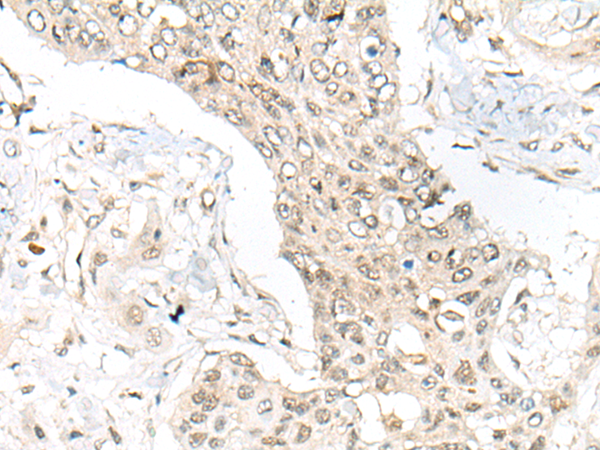

IHC positive control: |

Human prostate cancer and human gastric cancer |